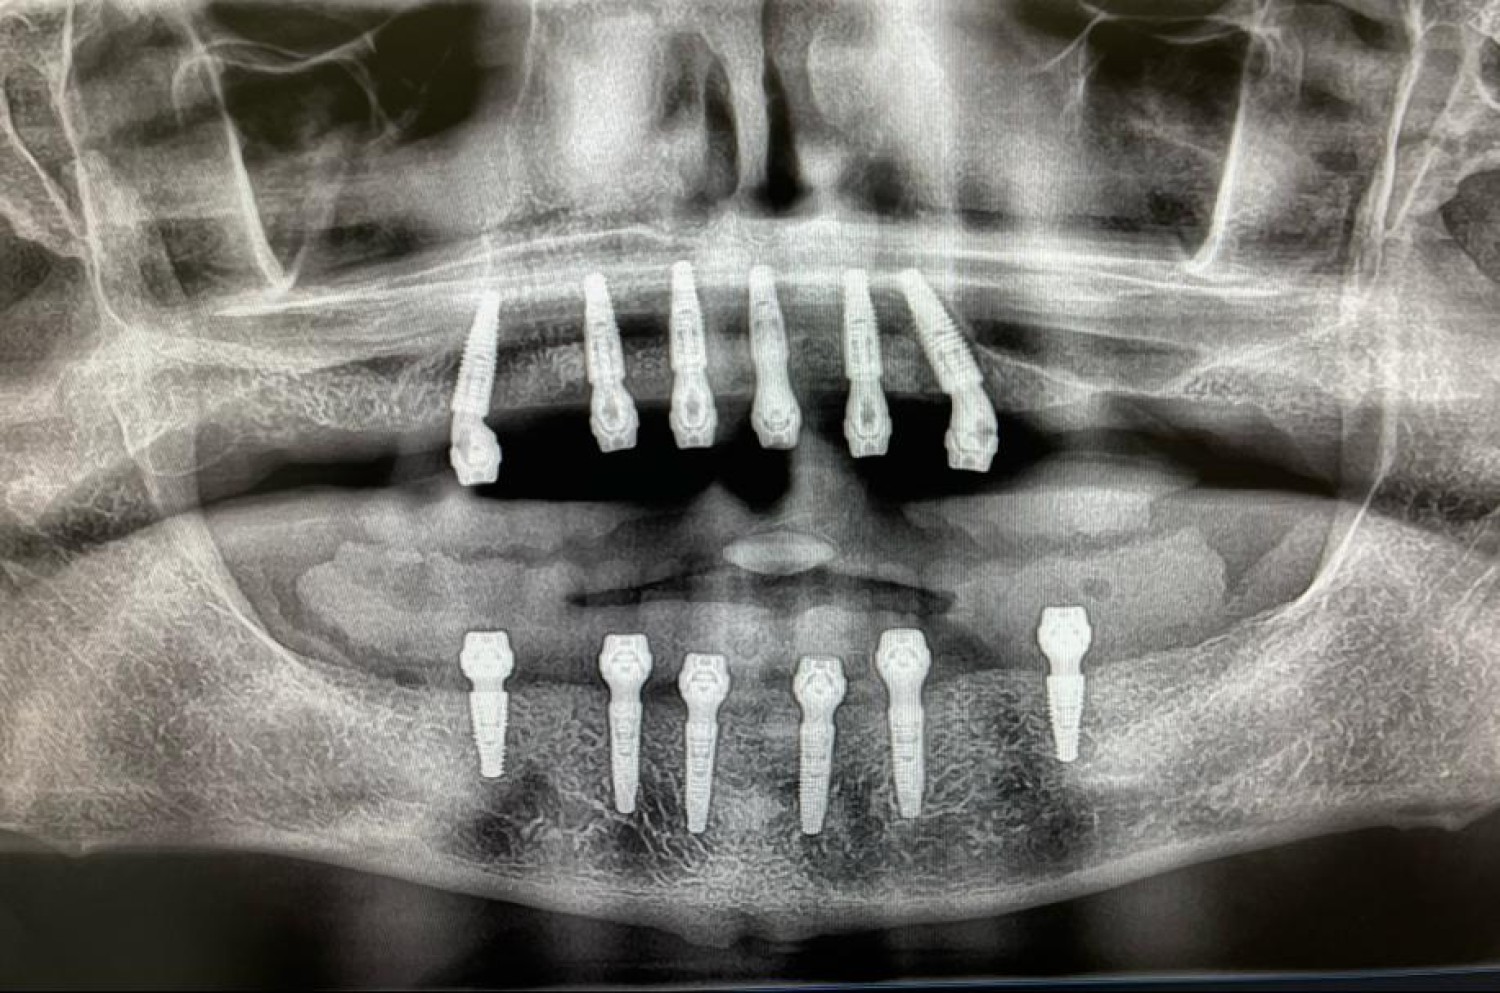

Find top-notch surgeons and dental equipment for W...

Dental crowns in Tijuana

Gum surgery in Tijuana